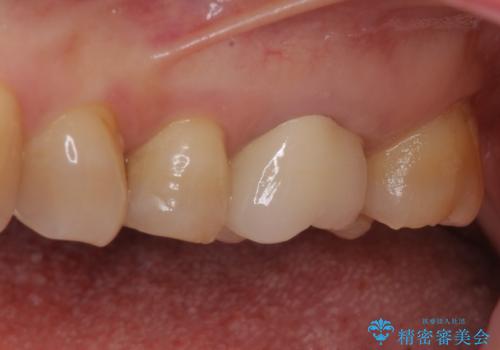

境目にものが詰まって気になる オールセラミッククラウン治療

- 奥歯に装着したクラウンの周りに汚れが溜まりやすいとのことで来院された患者様です。

既に装着されているクラウンの質は決して悪いものではありませんでしたが、患者様自身が非常に気にしていたため、作り替えの治療を行うこととしました。

クラウン装着後は、特にものが挟まる感覚もなく、快適に過ごすことができるようになりました。